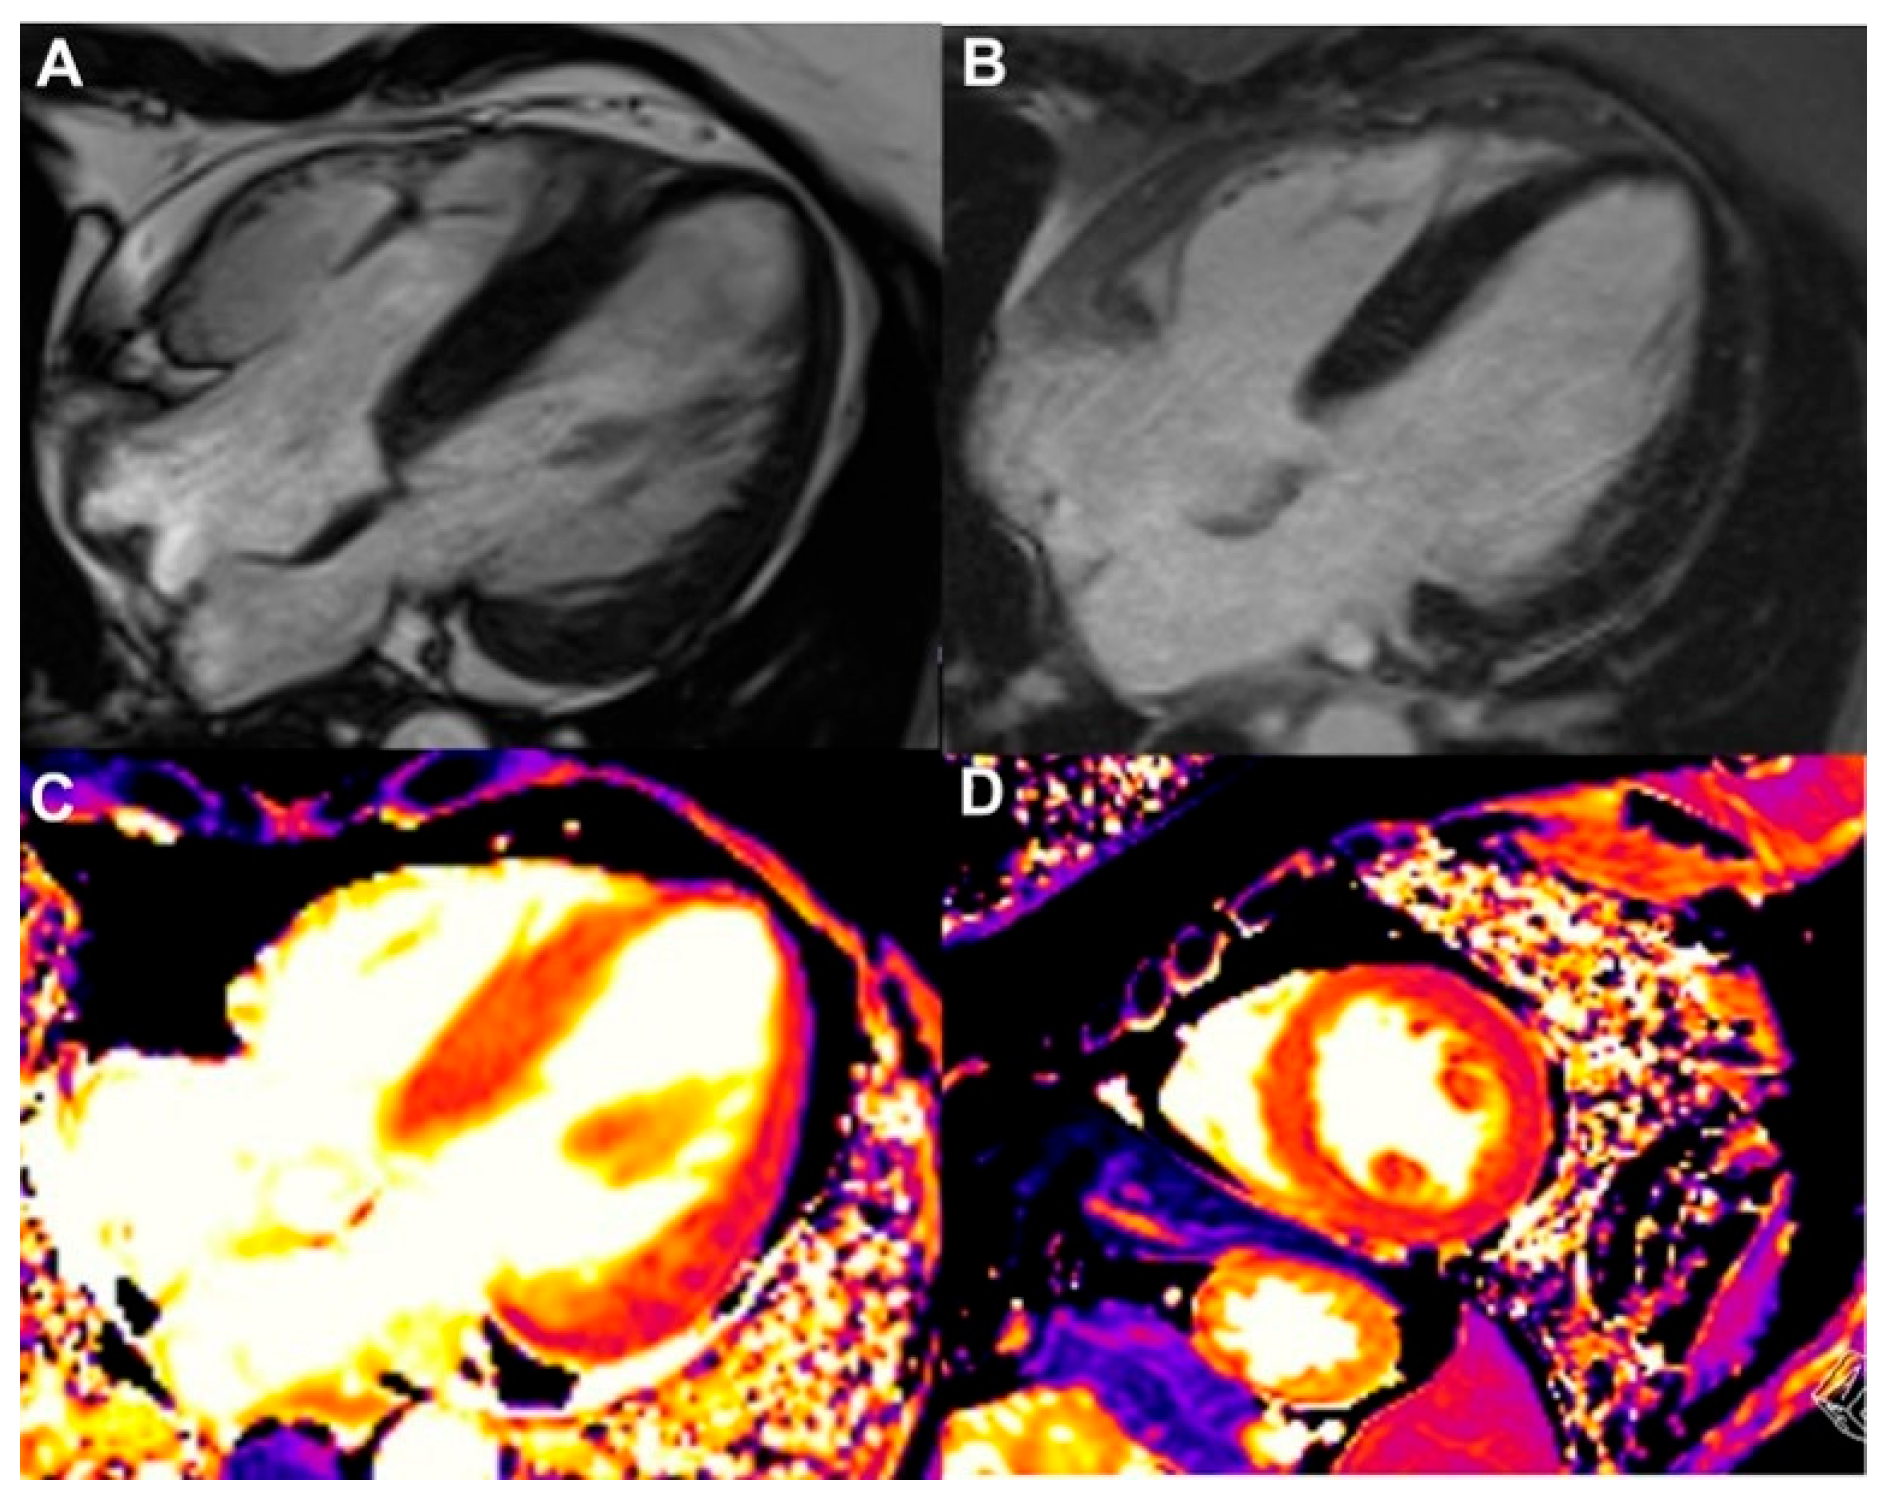

- Thavendiranathan, P.; Zhang, L.; Zafar, A.; Drobni, Z.D.; Mahmood, S.S.; Cabral, M.; Awadalla, M.; Nohria, A.; Zlotoff, D.A.; Thuny, F.; et al. Myocardial T1 and T2 Mapping by Magnetic Resonance in Patients With Immune Checkpoint Inhibitor–Associated Myocarditis. J. Am. Coll. Cardiol. 2021, 77, 1503–1516. [Google Scholar] [CrossRef]

- Messroghli, D.R.; Moon, J.C.; Ferreira, V.M.; Grosse-Wortmann, L.; He, T.; Kellman, P.; Mascherbauer, J.; Nezafat, R.; Salerno, M.; Schelbert, E.B.; et al. Clinical Recommendations for Cardiovascular Magnetic Resonance Mapping of T1, T2, T2* and Extracellular Volume: A Consensus Statement by the Society for Cardiovascular Magnetic Resonance (SCMR) Endorsed by the European Association for Cardiovascular Imaging (EACVI). J. Cardiovasc. Magn. Reson. 2016, 19, 75. [Google Scholar] [CrossRef] [PubMed]

- Ferreira, V.M.; Schulz-Menger, J.; Holmvang, G.; Kramer, C.M.; Carbone, I.; Sechtem, U.; Kindermann, I.; Gutberlet, M.; Cooper, L.T.; Liu, P.; et al. Cardiovascular Magnetic Resonance in Nonischemic Myocardial Inflammation. J. Am. Coll. Cardiol. 2018, 72, 3158–3176. [Google Scholar] [CrossRef]

- Burrage, M.K.; Ferreira, V.M. The Use of Cardiovascular Magnetic Resonance as an Early Non-Invasive Biomarker for Cardiotoxicity in Cardio-Oncology. Cardiovasc. Diagn. Ther. 2020, 10, 610–624. [Google Scholar] [CrossRef]

- Lerchner, T.; Mincu, R.I.; Bühning, F.; Vogel, J.; Klingel, K.; Meetschen, M.; Schlosser, T.; Haubold, J.; Umutlu, L.; Dobrev, D.; et al. Cardiac Magnetic Resonance Imaging in Patients with Suspected Myocarditis from Immune Checkpoint Inhibitor Therapy—A Real-World Observational Study. IJC Heart Vasc. 2025, 56, 101581. [Google Scholar] [CrossRef]